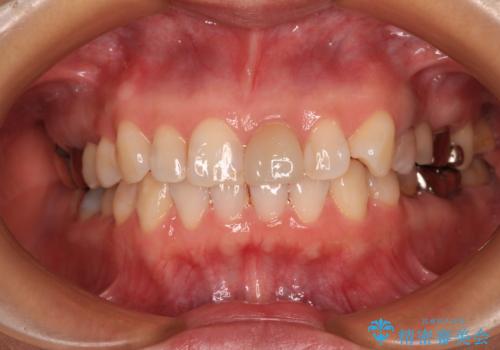

- 上下前歯のデコボコを気にして来院された患者様です。

カウンセリングにて詳しく話を聞いたところ、一番気になっているのは下顎前歯の叢生であり、上顎犬歯はあまり気になっていないとのことでした。

矯正治療は、歯の後戻りを抑制するために、治療終了後も保定装置をしっかりと使用していただくことが必須であるため、気になっている下顎だけを整えることで、その負担を半減できると考え、下顎のみの部分矯正として治療を行うこととしました。

装置としては、叢生の程度が強くなかったため、インビザラインの廉価版であるモデレート・パッケージを使用することとしました。